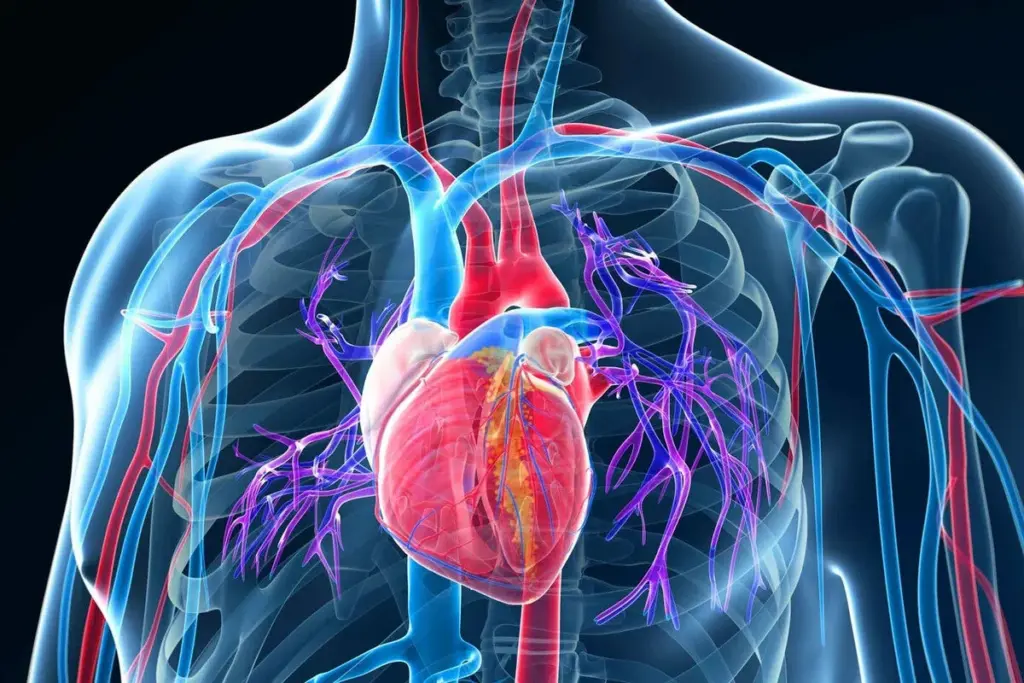

Coronary artery disease is a big problem worldwide, leading to serious heart issues. A key tool in diagnosing this disease is the fractional flow reserve (FFR). FFR measures how severe the narrowing is in the coronary arteries.

Healthcare providers use FFR to compare blood flow before and after a blockage. This helps them choose the best treatment. It’s essential for interventional cardiologists to plan effective care for their patients.

Understanding Coronary Physiology

Knowing about coronary physiology is key to treating heart issues well. It studies how the heart’s blood vessels work, both at rest and under stress.

Coronary autoregulation is a big part of this study. It shows how the heart’s blood vessels adjust to changes in pressure or demand. This ensures the heart gets enough oxygen and nutrients.

Normal Coronary Blood Flow

Normal blood flow to the heart is vital for its function. The coronary arteries bring blood to the heart muscle. This flow is controlled by many factors, like demand, nerves, and the lining of blood vessels.